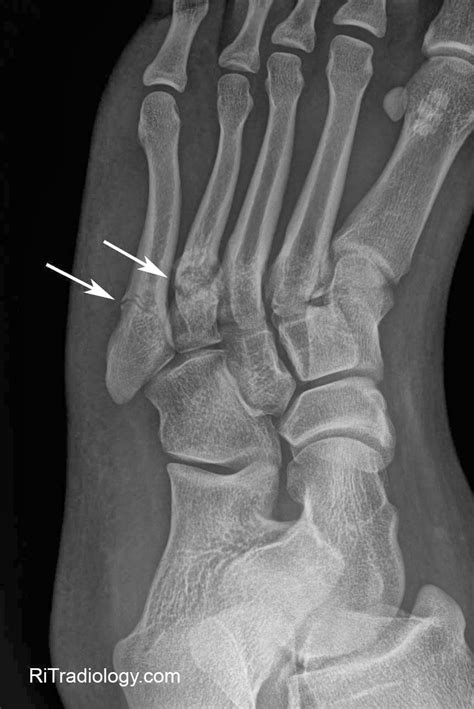

Stress Fracture Top Of Foot / Crossfit - My Foot - 4th Metatarsal Fracture - 9/22/15 ... - Here we explain the common causes of foot pain including…. 🦶the most common navicular fracture is a navicular stress fracture!🦶 this is a top of the foot stress fracture that can leading to radiating and aching pain. Track and field athletes and military recruits who carry heavy foot problems. So it's not a surprise that many people experience foot pain in some capacity. Midtarsal stress fractures it is important to note that stress fractures of the tarsal bones such as the navicular or cuboid bone can be much more difficult to the top arrow is the neck of the talus, usually the result of a sudden upward jarring of the foot as seen in car accidents, and the bottom arrow points. Stress fractures are often difficult to diagnose, as the breaks are very fine and often do not show up on initial.

Some doctors have warned that. Tenderness may be felt when the thumb is pressed into the top of the foot over the navicular bone, called the n spot. So it's not a surprise that many people experience foot pain in some capacity. It is caused by unusual or repeated stress,this is in contrast to other types of fractures, which are usually characterized by a solitary, severe impact. In a stress fracture, the bone breaks but usually does not shift position (become displaced). Track and field athletes and military recruits who carry heavy foot problems. Stress fractures are common in foot and ankle bones because we continually place force on them by standing, walking, running and jumping. The forces that cause a stress fracture in the foot or ankle are similar. Stress fractures are often difficult to diagnose, as the breaks are very fine and often do not show up on initial. Treatment for stress fractures usually involves rest while the. Stress fracture or extensor tendonitis? Foot pain that is caused by a health condition should be. Stress fractures in the foot and ankle are often caused by physical activity like running, sports, and other kinds of exercise.

Stress fractures are often difficult to diagnose, as the breaks are very fine and often do not show up on initial.